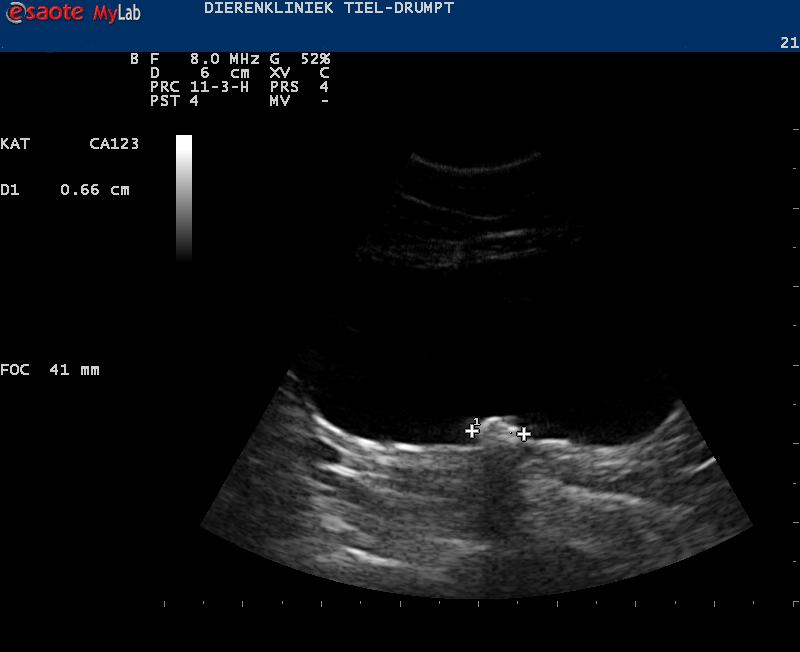

Zo kan er sprake zijn van zwelling of een gezwel bij de penis of een verstopping in de plasbuis door bijvoorbeeld samengeklonterd gruis, een blaassteentje of een plug (dit wordt gevormd door eiwitten, cellen, etc) die een verstopping kunnen geven.Ook structuren in de blaas kunnen de uitmonding verstoppen, zoals steentjes, poliepen, gezwellen, etc.

Het eerste dat moet gebeuren bij de behandeling is zorgen dat de urine uit de blaas kan, zodat de kat zijn gifstoffen kwijt kan. Hierbij, of direct hierna proberen we de oorzaak vast te stellen. Dit om te voorkomen dat er lang behandeld wordt zonder een goede kans op genezing.

De kater wordt in slaap gebracht, waarna er geprobeerd wordt om de plasbuis in de penis vrij te krijgen. In de meeste gevallen gaat het om een ontstekingsplug of gruis en in deze gevallen zal er een urinekatheter ingebracht worden. Deze wordt vastgehecht en moet een aantal dagen blijven zitten. De katheter zorgt voor een continue mogelijkheid tot het afvoeren van de urine, waarbij tevens de blaaswand rust krijgt. Na een aantal dagen spoelen en behandelen met medicatie halen we de urinekatheter eruit en zal er gecontroleerd moeten worden of de klachten niet terugkomen.